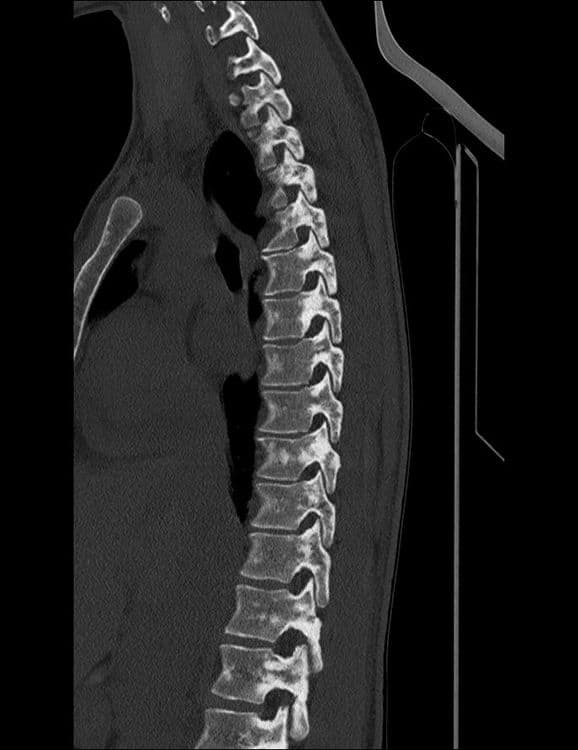

Attente osseuse axiale de la sclérose tubéreuse de Bourneville, ou complexe de sclérose tubéreuse (TSC).

CTMRI